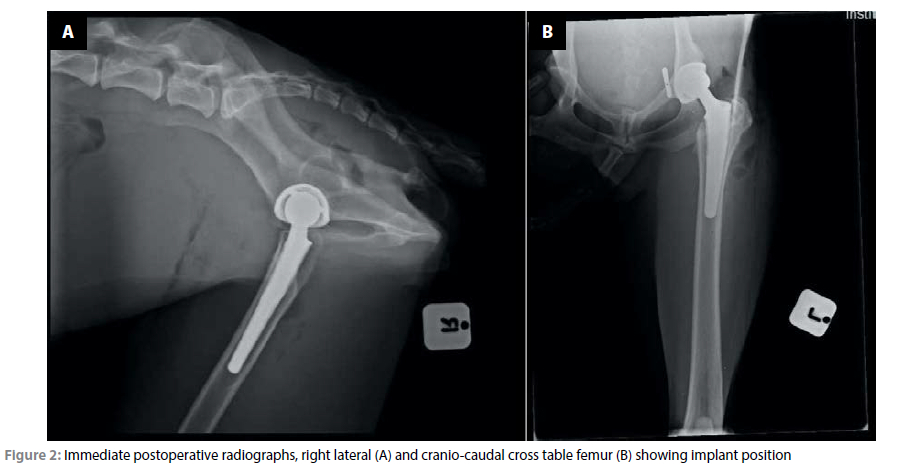

Plain film radiography showed cranio-dorsal coxo-femoral luxation with failure of the toggle rod (Figure 1).

Postoperative radiographs were taken prior to the patient recovering from anaesthesia to assess implant placement and angulation of the implants relative to each other (Figure 2). The postoperative position of the radiographs showed an angle of lateral opening of the acetabular cup of 45°, 2-3° of inclination and 15° of retroversion. The femoral stem was positioned with 2-3° of anteversion and mild cranial caudal tilting in the femoral canal.